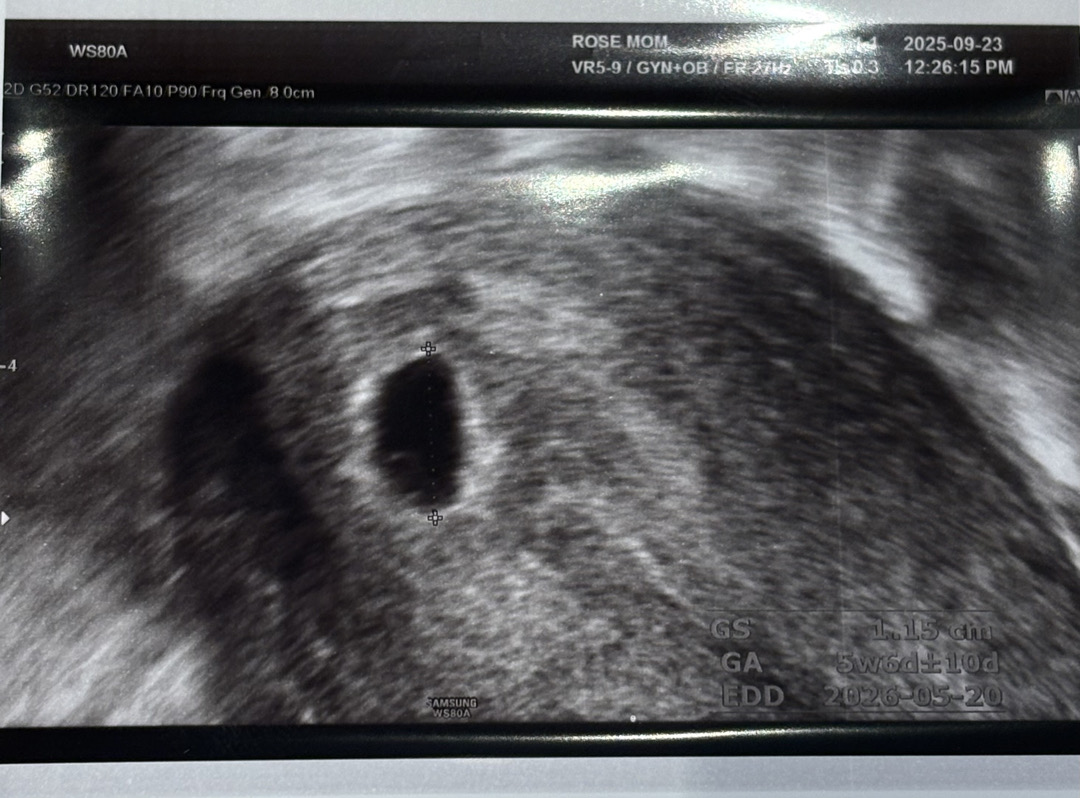

안녕하세요. 저번주 토요일 아기집 확인하고 일주일 뒤를 기다리고 있던 오늘로 5주3일차 예비맘입니다. 어제 밤 살짝 배가 뻐근하고 말아서 별 신경 안쓰고 잠들었는데 오늘 아침에 작은 연분홍혈이 휴지에 닦여서 병원에 다녀왔습니다🥹 초음파로 확인하는데 아기집이랑 난황까지 확인했어요! 자궁에 피고임은 없다고 하는데 왜 작은 출혈이 있을까요 하니까 살짝 유산기있는거 같다고 유산방지약 처방받아왔네요ㅠ 이번주 토요일에 와도 된다고는 하는데...걱정이 살짝쿵 됩니다. 아기집 크기는 1.15cm이고 난황이 보이는 상황입니다!!! 우리애기 괜찮겠죠..? 유산방지약은 먹으니까 어지럽고 잠이 쏟아져요ㅠㅠㅠㅠ 토요일가면 심장소리도 들릴겠죠 ?? 걱정이 몰려오는데 이런경우에는 어떻게 멘탈을 잡아야할까요? 🥹🥹🥹